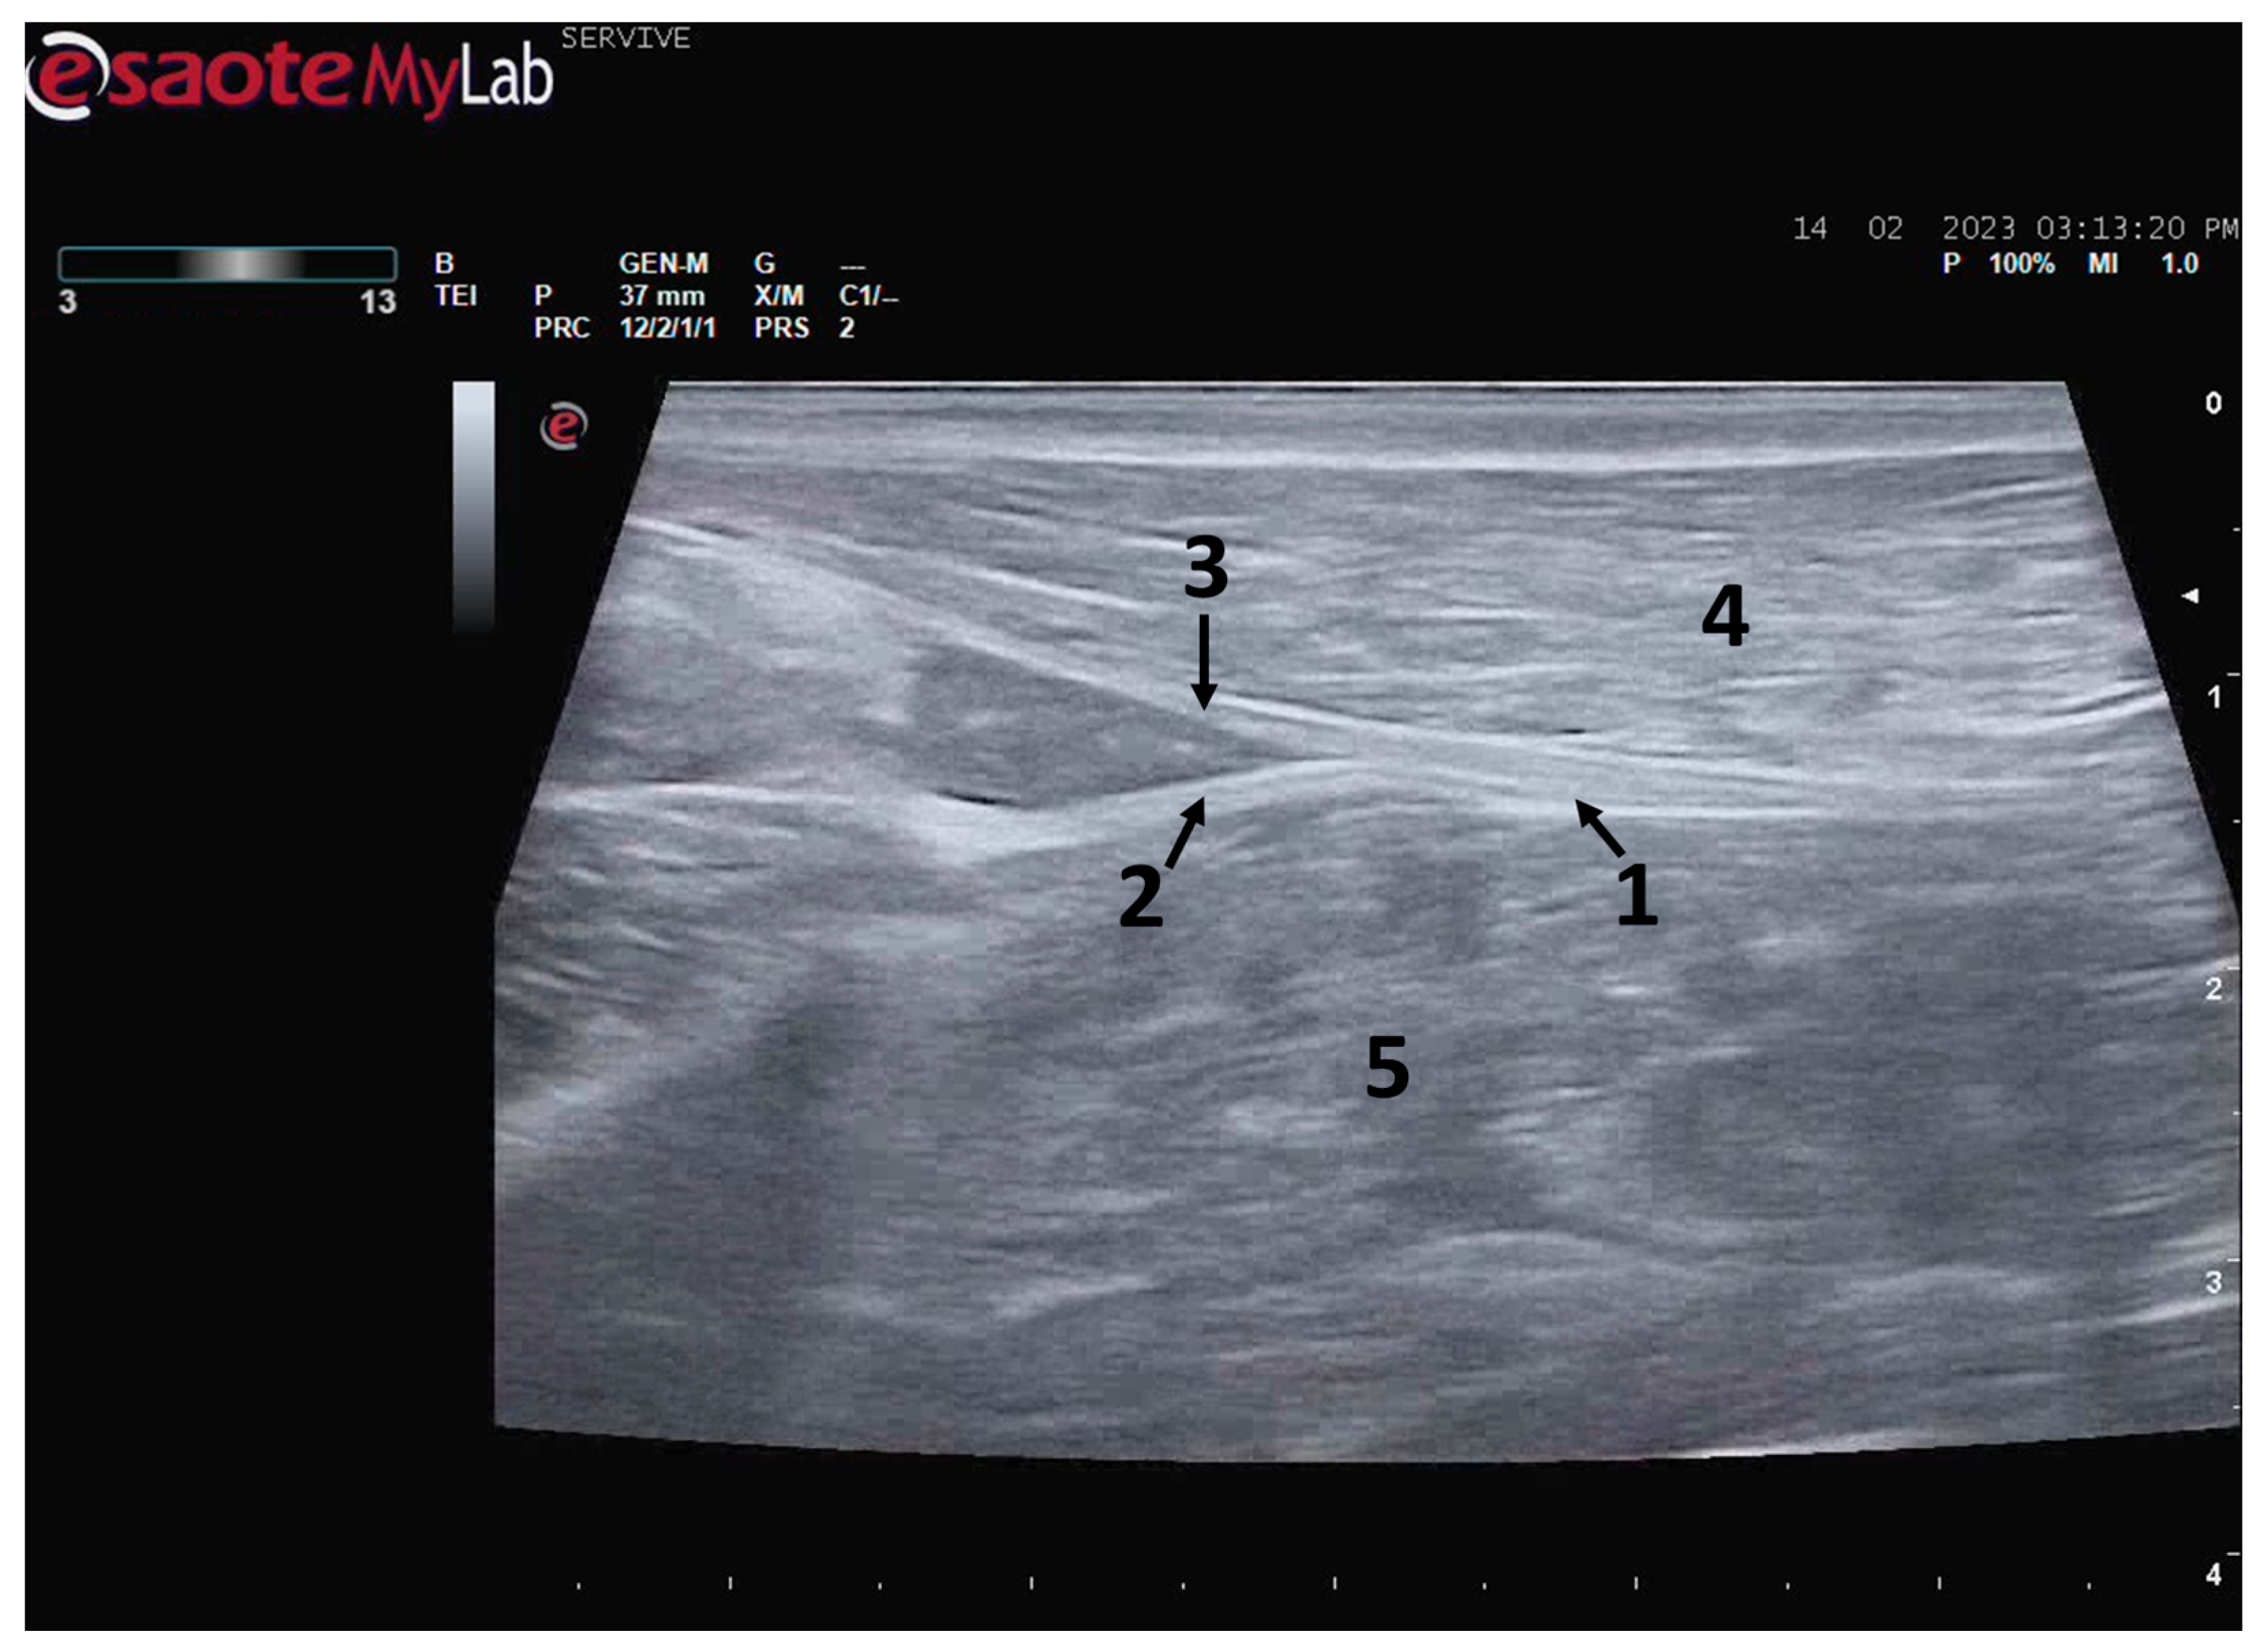

At the level of the stifle, and with great interindividual variation, the two branches of the sciatic nerve, the common peroneal nerve, and the tibial nerve, are easily observable and distinguishable, diverging from the main nerve (Figure 5). Both the sciatic nerve and its branches appear as hypoechogenic neuronal tubular structures (nerve fascicles and the perineurium) surrounded by a hyperechogenic envelope corresponding to the connective tissue nerve wrappings (epineurium) (Figure 3, Figure 4 and Figure 5). The most lateral nerve, appearing dorsally on the ultrasound image, corresponds to the common peroneal nerve and imagiologically has a slightly smaller diameter than the tibial nerve, which is more medial and appears ventrally on the ultrasound image. Accompanying both nerves distally, there is a tendency for a slight decrease in their diameter before the final ramifications, but the intended site for inducing injury to the common peroneal nerve is proximal to the point where the decrease in diameter occurs.

Figure 5.

Ultrasound image of the left sciatic nerve and its ramifications in a sheep: (1) sciatic nerve, identified by an arrow; (2) tibial nerve, identified by an arrow; (3) common peroneal nerve, identified by an arrow; (4) biceps femoris muscle; (5) adductor muscles.